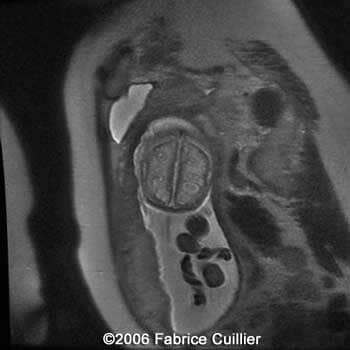

Follow-up scans at 30 and 31 weeks demonstrated a progressive hydrocephaly. An MRI was performed. The parents were informed about the fetal prognostic. They decided to interrupt the pregnancy (girl, 1500 g). They refused the anatomical-pathological examination. The fetus did not have any external anomalies.

MRI at 30 weeks showing parasitic cystic abscess on the parenchyma brain and partial left cerebellar hypoplasia

11